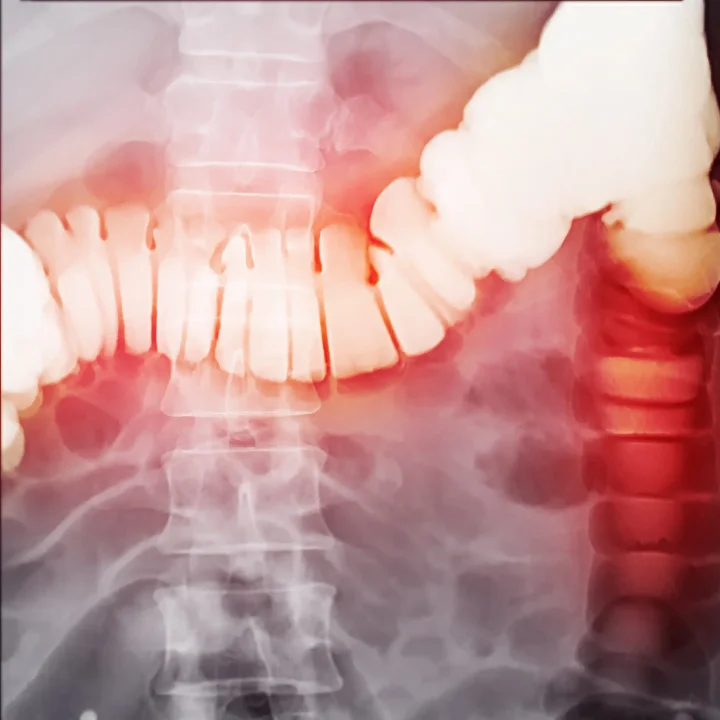

Konuya ilişkin önemli bilgiler paylaşan Prof. Dr. Esin Korkut, “Divertikül kanaması, kalın bağırsak duvarında oluşan küçük cep şeklindeki çıkıntıların (divertikül) damarlarında meydana gelen yırtılma veya zedelenmedir. Genellikle ani gelişir ve ağrısız bir bağırsak kanaması olarak kendini gösterir.” dedi.

Divertiküllerin özellikle kalın bağırsakta, küçük baloncuklar şeklinde ortaya çıktığını belirten Prof. Dr. Korkut, “Divertiküller yaşla birlikte özellikle 50 yaş üstü, yoğun kabızlık sorunu olan hastalarda görülüyor. Çoğu zaman herhangi bir şikâyet yaratmadan kolonoskopide tesadüfen tespit ediliyor. Ancak komplikasyonlar ortaya çıktığında ciddi ağrı ve yoğun kanamaya yol açabiliyor” dedi.